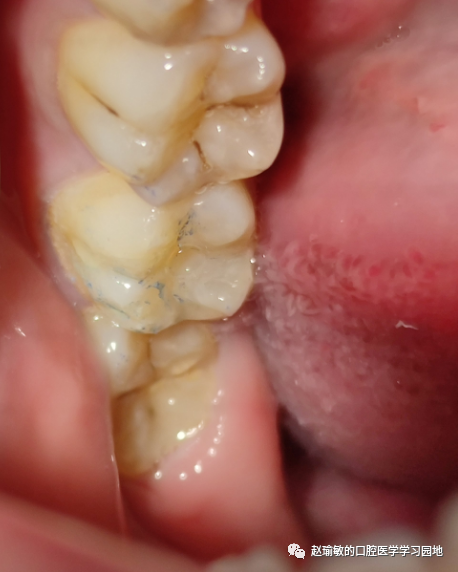

颌面放上流体树脂,这里是第一个坑了,要用粘接剂毛刷等按在流体树脂里再光固化。我就是没有放东西,光固化10秒,结果发现很难取下来,只能硬抠+快机磨。最后抠下来了,但是舌侧那部分印章断了。

这是抠下来的印章。